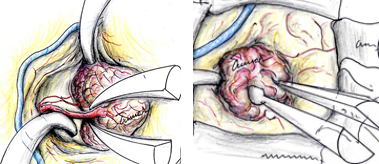

腎臓癌の脳転移巣は腫瘍サイズが小さい割に脳浮腫が強い場合が多いです。写真で呈示した如く転移性脳腫瘍の肉眼所見は、血管奇形や血管腫と似ており正常脳との境界がわかりやすいため比較的摘出は容易です。また広範囲な脳浮腫も腫瘍を全摘すると消失します。

従って腫瘍サイズが小さい場合でも、当科では可能な限り転移性脳腫瘍に対して積極的に摘出手術を行っています。特に頭蓋内を占拠するような病変については患者さんのQOL(生活の質)に留意した手術を行い、たとえ末期癌であっても在宅療養への後押しとなるような治療の提供を考慮しています。